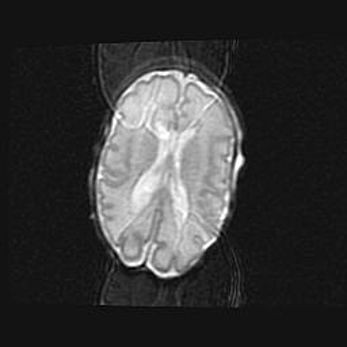

Сообщающаяся гидроцефалия. Кистозная энцефаломаляция головного мозга.

Возраст: 3 месяца 4 дня

Вес: 3100 г

Пол: женский

Окружность головы: 34 см

Срок гестации: 31 неделя

Кистозная энцефаломаляция головного мозга - одна из форм поражения головного мозга в детском возрасте. Характеризуется возникновением множественных и распространённых кист в коре, белом веществе и подкорковых образованиях головного мозга у плодов, новорождённых и детей раннего возраста. Развитие кистозной энцефаломаляции связано с внутриутробной асфиксией и гипотонией, родовой травмой, тромбозом синусов, пороками развития сосудов, инфекциями, сепсисом и другими причинами. Наиболее значимые инфекционные агенты: вирусы простого герпеса, цитомегалии, краснухи, токсоплазмы, энтеробактерии, золотистый стафилококк и другие.